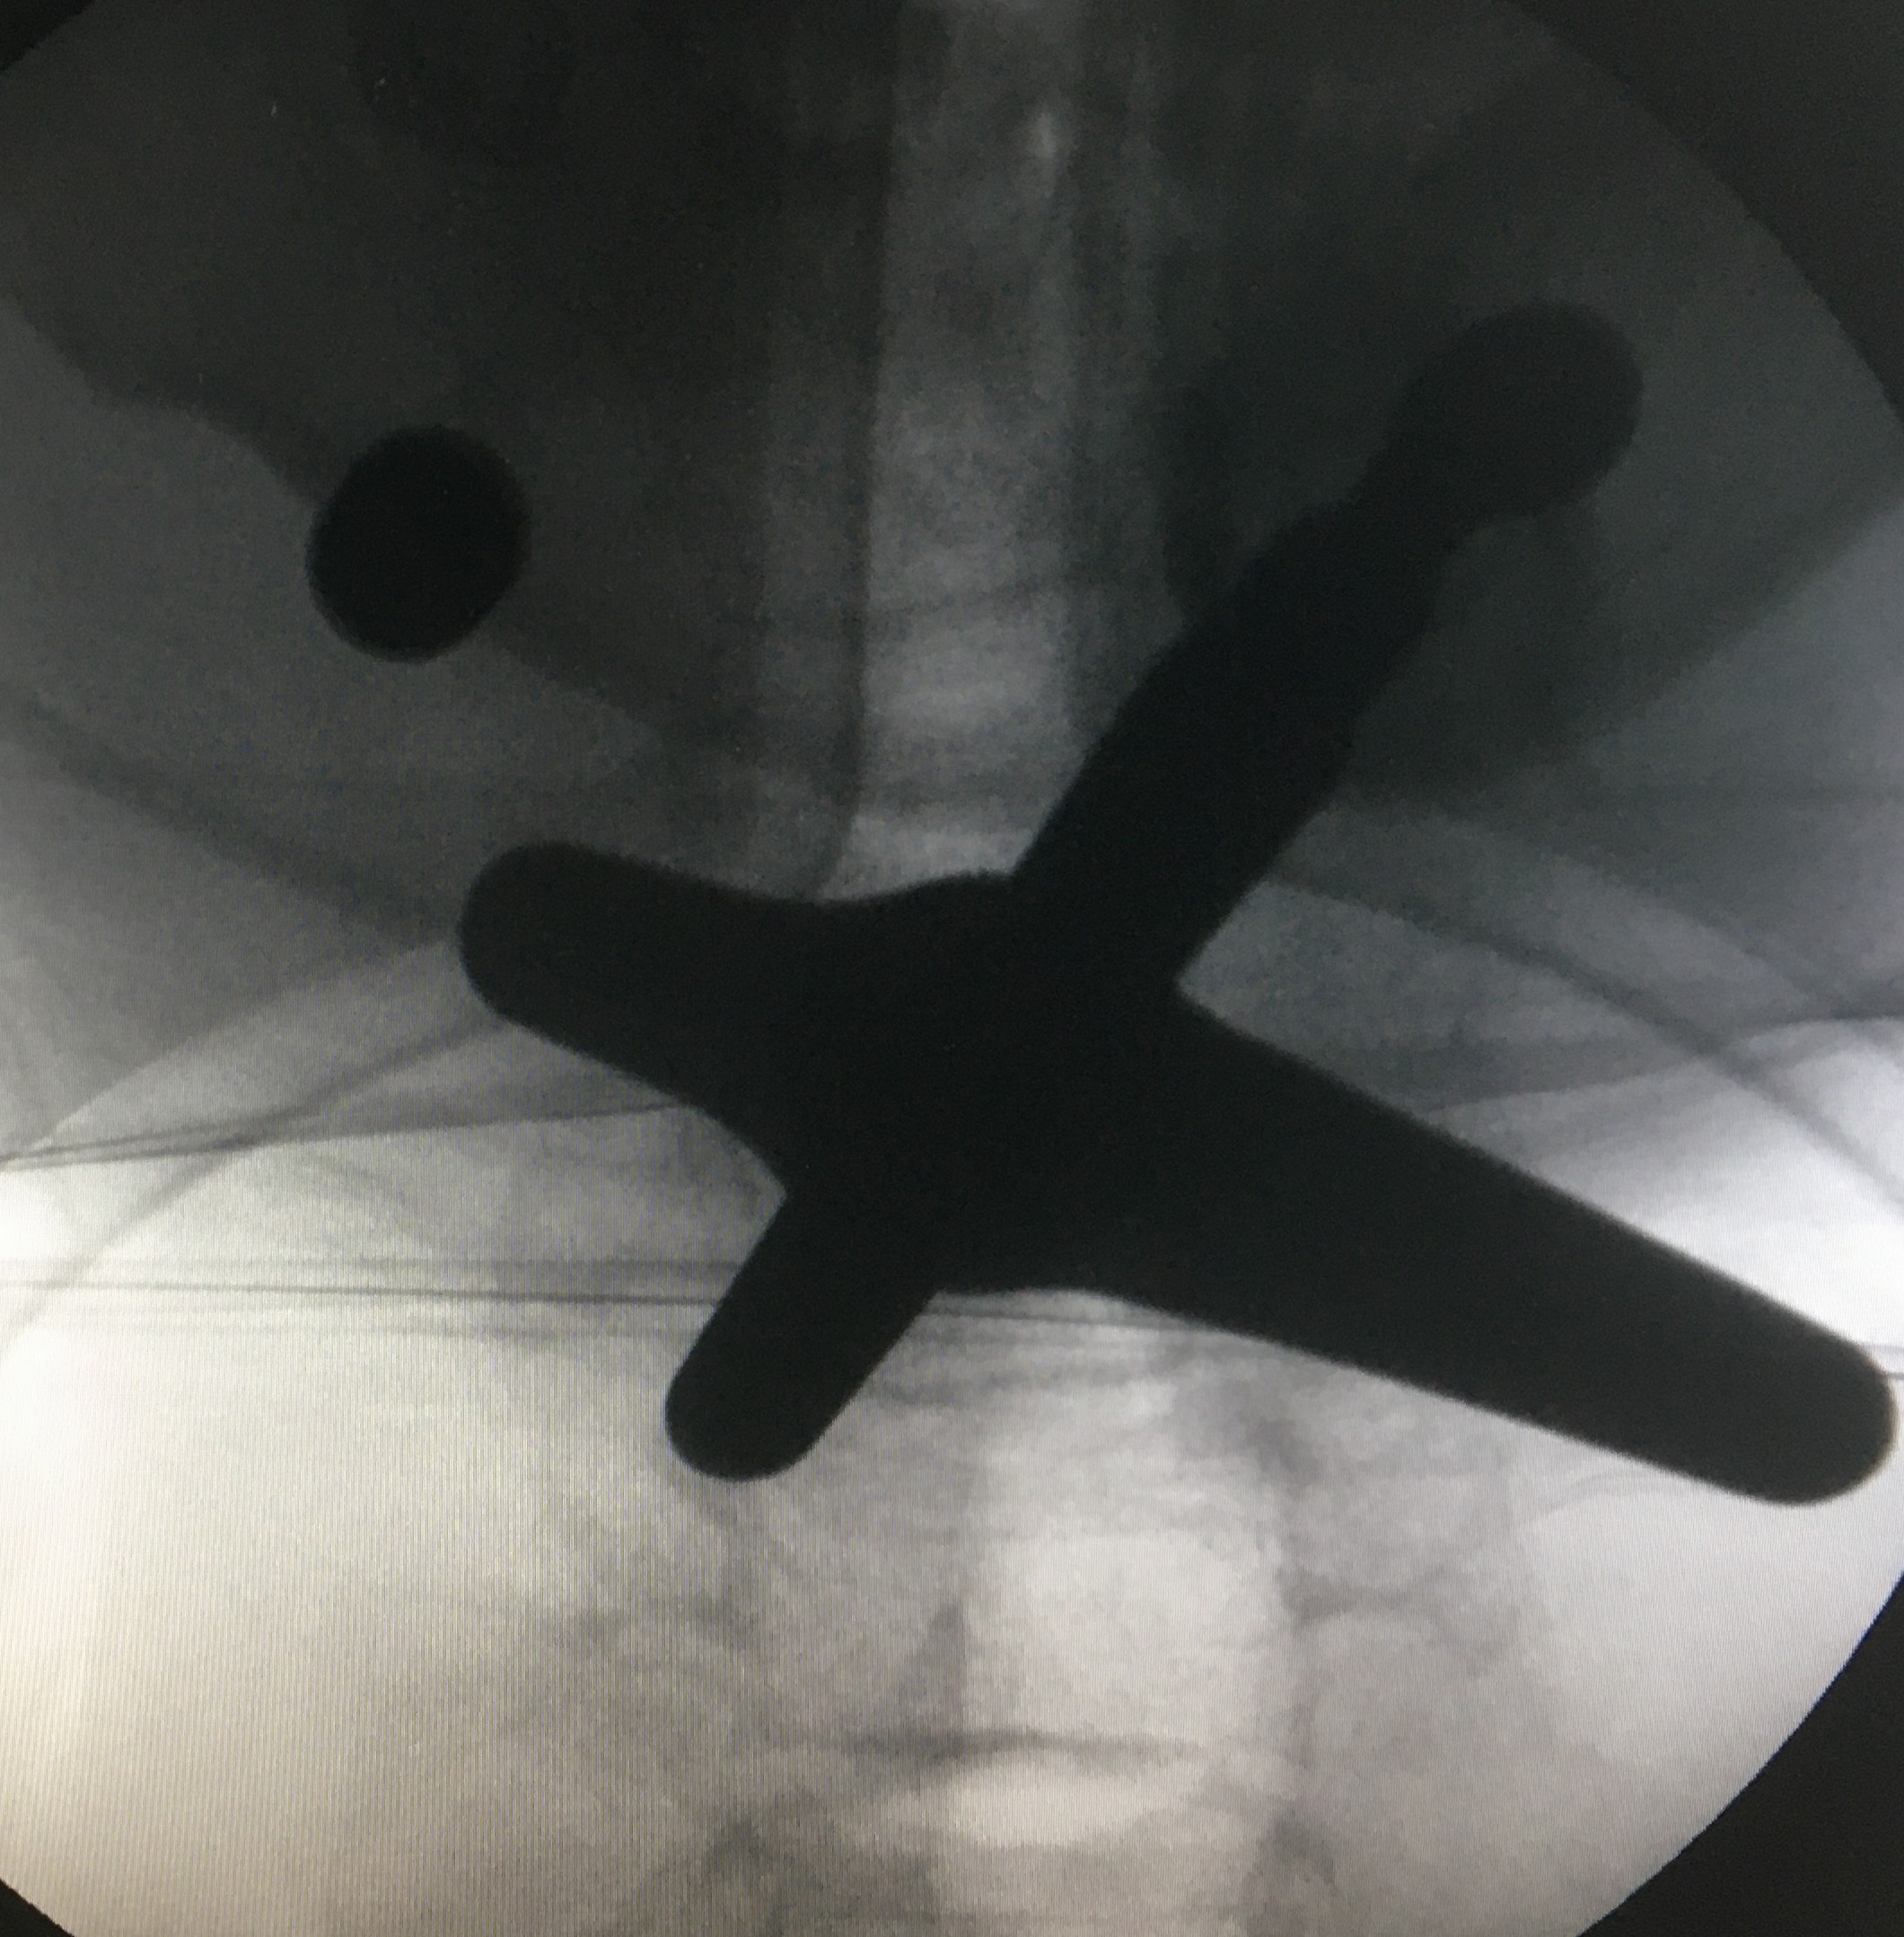

慕名找到陈明博士后,一个局麻的微创孔镜手术,只有1cm大小的切口,很小的费用就彻底恢复了,邓先生高兴万分,不由自主地说:人的认知是决定人命运的关键呀。

而手术治疗又分为两类:开放手术和微创手术。每个人都要根据自身的情况,选择最适合自己的方法,一般来说,单纯的突出,没有明显钙化的患者可以首先考虑局麻的微创治疗,但是较为严重的颈椎病可能就需要做开刀治疗了,不管哪种方案,在有经验的医生手上都是安全、有效的。